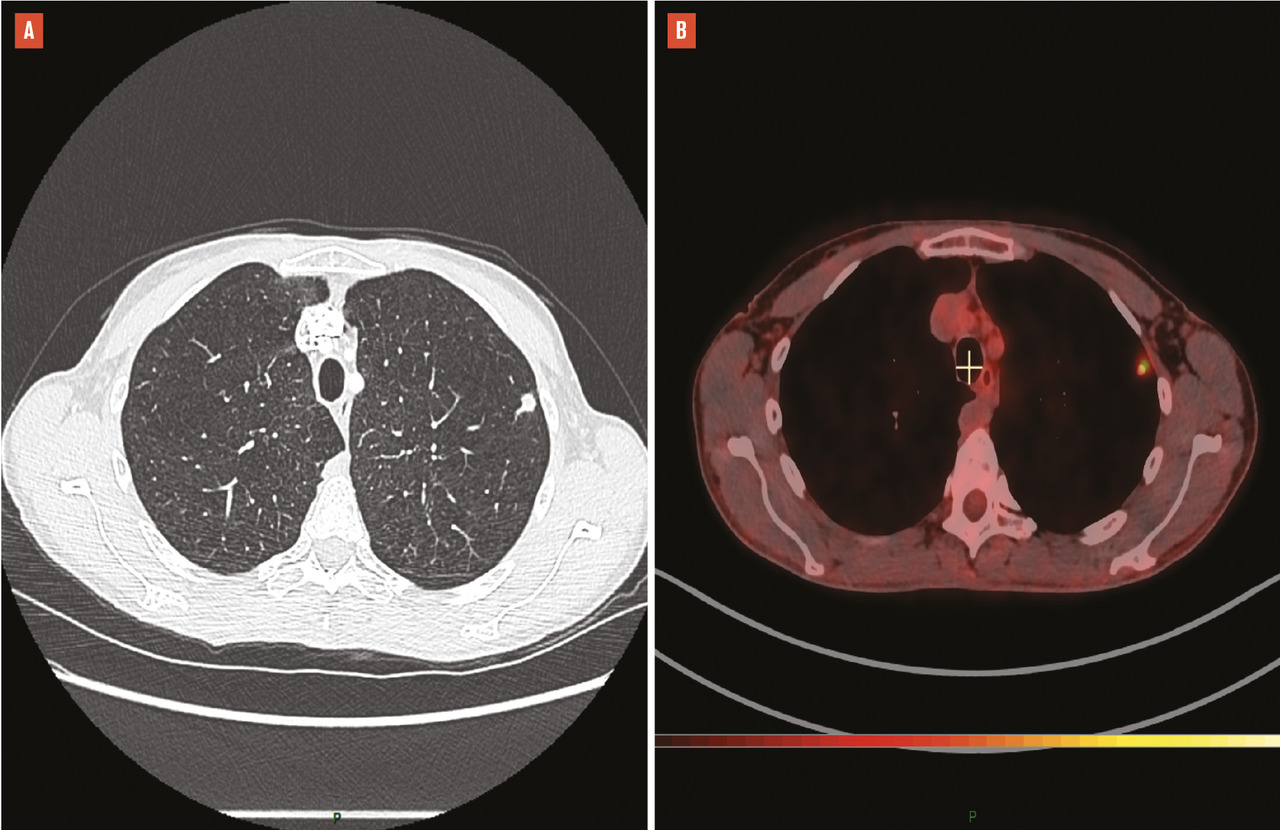

Le diagnostic du cancer pulmonaire, comme le bilan d’extension, a bénéficié de l’essor des scanner hélicoïdaux, dont les progrès techniques ont permis une imagerie toujours plus précise et rapide, avec une irradiation qui n’a cessé de décroître au fil du temps.1 La tomodensitométrie couplée à la tomographie à émission de positons (TEP/TDM), rapidement démocratisée dans la décennie 2000-2010, a permis un bilan d’extension plus exhaustif, complété par l’imagerie par résonance magnétique (IRM) cérébrale, bien que son exactitude n’atteigne pas 100 %, avec des faux négatifs notamment liés à la taille infracentimétrique de certaines lésions. Les faux positifs justifient une vérification histologique systématique des images ganglionnaires médiastinales, qui a bénéficié de l’essor et de la diffusion, dans les services de pneumologie, de l’écho-endoscopie bronchique avec une exploration exhaustive du médiastin et un diagnostic histologique précis de l’extension ganglionnaire des cancers bronchopulmonaires.